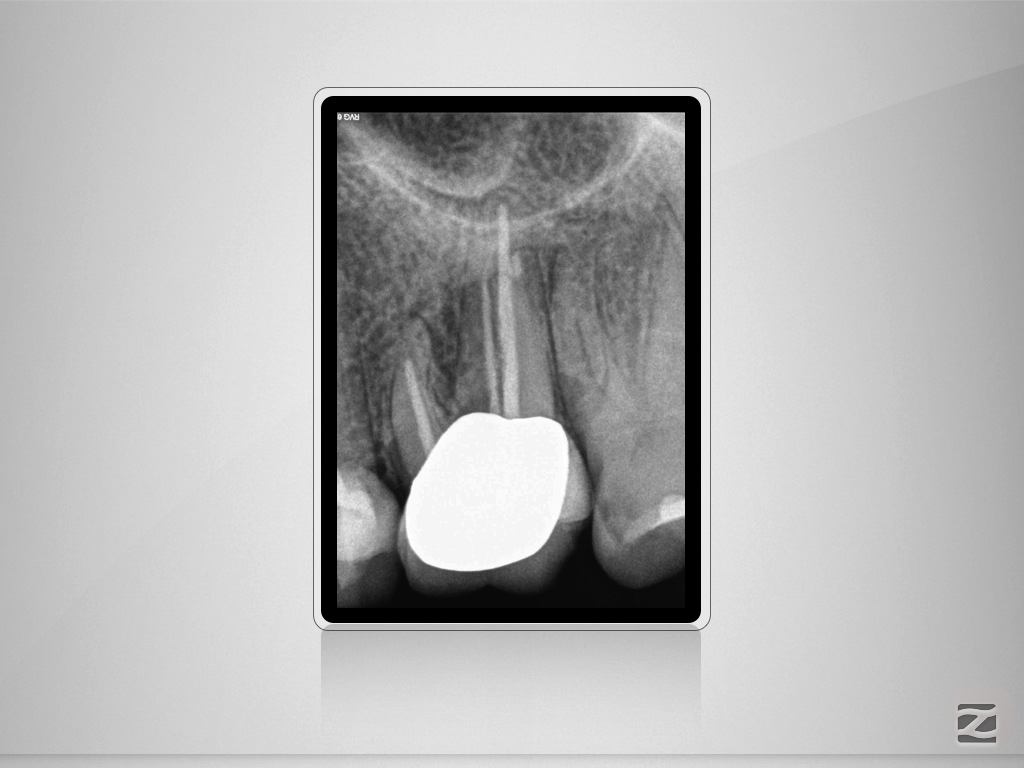

2526d-001

Enter Sandman